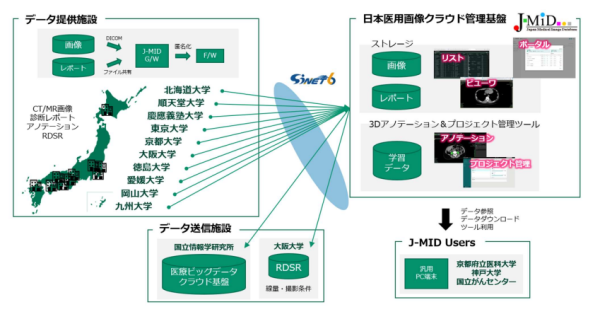

公益社団法人日本医学放射線学会(事務局所在地:東京都文京区、理事⾧:青木 茂樹、以下 JRS)、順天堂大学(本部所在地:東京都文京区、学⾧:新井 一、大学院医学研究科放射線診断学 教授:青木茂樹)、富士フイルム株式会社(本社:東京都港区、代表取締役社⾧・CEO:後藤 禎一、以下富士フイルム)は、国内の医療機関※1 で撮影された医用画像を集約し一元管理するデータベース「日本医用画像データベース(Japan-Medical Image Database、以下 J-MID)」向けに次世代クラウド管理基盤を構築した。次世代クラウド管理基盤は、富士フイルムのクラウド型医用画像管理基盤を活用したもので、4月3日、稼働を開始した。次世代クラウド管理基盤を採用した J-MID は、国内のどこからでも高速な医用画像の登録・参照・検索を可能にし、医用画像を活用した画像診断支援 AI 技術の研究開発を促進する。

J-MID は、JRS が 2018 年に稼働させた、医用画像を集約し一元管理するデータベースである。JRS は、J-MID の活用を推進し、画像診断支援 AI 技術はじめ、画像診断の精度向上や効率化を支援する技術の研究開発を促進させることを目指す。J-MID には、これまでに国内の医療機関・研究施設 10 施設※1 から提供された 4 億枚を超える CT・MRI 画像が、所見などを含むレポート情報とともに登録されている。現在、J-MID を活用した研究開発をリードする研究代表施設である順天堂大学や、その他複数の共同研究施設※2 において、J-MID に登録された画像や情報をもとに、画像診断の精度向上や効率化に寄与するさまざまな技術の研究開発が進められている。

JRS と順天堂大学は、J-MID の活用を加速させるため、データベースのサーバーを特定の場所に設置して管理する従来の方式から、クラウド上で管理する方式に移行することを決定した。次世代クラウド管理基盤を採用した J-MID は、国内のどこからでも、高速かつ簡便な画像の登録・参照・検索を可能にする。また、画像診断支援 AI 技術などの研究開発プロセスにて医用画像を AI に学習させるために必要なデータ加工(アノテーション※3)を 3 次元領域で行うツール「3D アノテーションツール」や、データベース上に登録された大量の画像の活用状況をモニターできる「ユーザーポータル・ダッシュボード」など、効率的な研究開発を支援する豊富な機能も搭載する。

※1 J-MID データ提供施設:順天堂大学、九州大学、慶應義塾大学、大阪大学、岡山大学、東京大学、京都大学、北海道大学、徳島大学、愛媛大学。

※2 J-MID 共同研究施設:順天堂大学、九州大学、慶應義塾大学、大阪大学、岡山大学、東京大学、京都大学、北海道大学、徳島大学、愛媛大学、京都府立医科大学、神戸大学、国立がんセンター中央病院、国立情報学研究所。

J-MID は、日本医学放射線学会が、2018 年に、日本医療研究開発機構(AMED)の支援を受けて稼働させた、国内の医療機関で撮影された医用画像を集約し一元管理するデータベースである。JRS は、J-MID の活用を通して、画像診断支援 AI 技術をはじめ、画像診断の精度向上や効率化を支援する技術のほか、画像診断装置やシステムの適正使用、画像標準化、被ばく管理など、放射線医療の向上に向けた研究開発を推進する。2019年より順天堂大学(大学院医学研究科放射線診断学 教授:青木茂樹)が研究代表施設として J-MID を活用した研究開発をリードしている。現在、データ提供施設として国内計 10 施設、共同研究施設として国内計 14 施設が J-MID に参画する。